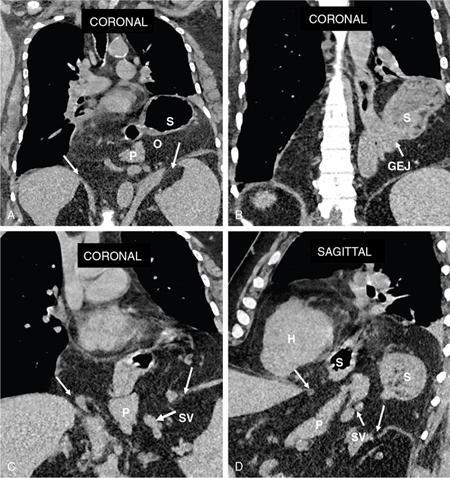

Swarup Nellore, Soumil Vyas, Ujwal Bhure, Ankit Jain, Richa Kothari, Daksh Mehta, Divya Kantesaria, Disha Lokhandwala, Karthik Ganesan The stomach is the most dilated portion of the gastrointestinal tract positioned between the oesophagus and the small intestine occupying the epigastrium, left hypochondrium and umbilical regions of the abdomen performing a multitude of functions including storage and mixing of food and controlling the passage of food into the intestine. Anatomically, the stomach is divided into the following parts (Fig. 8.2.1): the gastric cardia is the portion immediately adjoining the oesophageal opening into the stomach. The fundus is the dome-shaped part above the horizontal plane of the cardiac orifice which undergoes receptive relaxation and is the site of the autonomic pacemaker. The body is the largest part of the stomach extending from the cardiac orifice to the level of incisura angularis (notch like bend in the mid lesser curvature) containing majority of parietal cells (which secrete hydrochloric acid), chief cells (pepsinogen) and enterochromaffin-like cells (ECL). The pylorus is the tubular distal portion of the stomach which is further divided into the gastric antrum and pyloric canal. The pyloric antrum containing G-cells producing gastrin extends from the incisura angularis up to the pyloric sphincter which is an anatomical sphincter formed by concentric thickening of the circular muscle coat and encircles the narrow-slit like pyloric canal. The left dome of diaphragm and oesophagus lie superior to the stomach while the greater omentum and pancreas lie inferiorly. Spleen and liver lie on either side laterally while the transverse mesocolon is located inferolaterally. Diaphragm, greater omentum, left lobe of liver and anterior abdominal wall are anteriorly related to the stomach and contents of lesser sac including pancreas, spleen, splenic artery, transverse mesocolon, left kidney and adrenal gland lie posteriorly. The stomach is embryologically derived from the primitive foregut and is suspended anteriorly by the ventral mesogastrium and posteriorly by the dorsal mesogastrium. During development as the stomach rotates, the peritoneum grows and condenses to form perigastric ligaments, which contain blood vessels, lymphatics, lymph nodes, nerves and fat. The liver forms in the ventral mesogastrium, which develops into the falciform ligament, gastrohepatic ligament (GHL) and hepatoduodenal ligament (HDL). The spleen and pancreas form within the dorsal mesogastrium, which fuses with the posterior abdominal wall to form the gastrocolic ligament (GCL), gastrosplenic ligament (GSL) and splenorenal ligament (SRL). The perigastric ligaments are identified anatomically by the vessels contained in them (Fig. 8.2.2). The gastric cardia and lesser curvature of the stomach are attached to the inferior surface of liver by the lesser omentum by the gastrohepatic ligament respectively which contains the left and right gastric vessels. The inferior free edge of the gastrohepatic ligament extends inferiorly as the hepatoduodenal ligament between the porta hepatis and proximal duodenum gastrophrenic ligament extends between the stomach and the left hemidiaphragm. The gastrocolic ligament identified by the left and right gastroepiploic vessels, connects the greater curvature of the stomach to the anterior surface of the transverse colon. This ligament extends inferiorly as the greater omentum which is a double-layered peritoneum forming a drape anterior to the bowel loops. The gastrosplenic/lienogastric ligament bridges the posterolateral wall of the fundus and greater curvature along the proximal body of the stomach to the splenic hilum and contains the short gastric vessels. The gastrosplenic ligament is contiguous with the lienorenal ligament and both these structures constitute the lateral boundary of the lesser sac. Macroscopically the stomach shows a thick vascular mucosal lining in the form of longitudinal folds called gastric rugae. Microscopic layers of the stomach include mucosa, submucosa, muscularis externa and serosa. The mucosa includes surface mucus cells with simple columnar epithelium, gastric pits, gastric glands, lamina propria and muscularis mucosa. Submucosa includes connective tissue with submucosal Meissner’s plexus. Muscularis externa comprises three smooth muscle layers (longitudinal, circular and oblique) and Auerbach myenteric plexus. The outermost layer called serosa consists of loose connective tissue and visceral peritoneal lining. The arterial supply of stomach is constituted by the branches of celiac artery predominantly in the form of two anastomotic arcades along the lesser and greater curvature. Left gastric artery, a direct branch of the celiac trunk supplies the upper part of the lesser curvature while the lower part is supplied by the right gastric branch of the common hepatic artery arising at the upper border of pylorus. The left gastroepiploic artery, a branch of splenic artery, supplies the upper part of greater curvature and the inferior portion is supplied by the right gastroepiploic artery which is a branch of the gastroduodenal artery. The fundus additionally receives few small short gastric branches from the splenic artery. The veins follow the arteries in their nomenclature. Left and right gastric vein show direct drainage into the portal vein. The splenic vein derives flow from the short gastric and left gastroepiploic vein whereas the right gastroepiploic vein drains into the superior mesenteric vein. Pylorus can be surgically delineated by the prepyloric vein of Mayo lying on its anterior surface. Intrinsic nerve supply consists of the myenteric plexus of Auerbach and submucosal plexus of Meissner. Extrinsic nerve supply consists of sympathetic and parasympathetic components. Sympathetic nerve supply arises from T5 to T9 spinal cord segments supplying the celiac plexus via the greater splanchnic nerve. The plexuses then travel along the respective branches of celiac artery supplying the stomach. Parasympathetic nerve supply is derived from oesophageal plexus of vagus dividing into two vagal trunks. Right (posterior) vagus gives off the posterior gastric branch also called the criminal nerve of Grassi supplying the cardia and fundus of stomach. Right vagus then gives off a celiac branch and continues along lesser curvature of stomach as the posterior gastric nerve of Latarjet supplying the antrum, body and pylorus. Left (anterior) vagus gives off a hepatic branch then continues along the lesser curvature as the anterior nerve of Latarjet supplying the antrum, body and pylorus. Crow’s feet innervation to antropyloric area are important surgical landmarks preserved during highly selective vagotomy receiving branches from both major nerve trunks (anterior and posterior) at the incisura angularis. Anatomical lymphatic drainage is divided into three areas. Area I is the superior two-thirds of stomach draining via the nodes along left and right gastric vessels into the aortic nodes. Area II includes the right two-thirds of the inferior one-third which drains through the nodes along right gastroepiploic vessels via the subpyloric nodes into aortic nodes. Area III includes left one-third of greater curvature draining via short gastric and splenic nodes into suprapancreatic nodes and ultimately into aortic nodes. Gastric lymph node stations are divided into 4 levels with 16 lymph node stations: Paraesophageal nodes below the diaphragmatic hiatus (17) and above the diaphragmatic hiatus (18) are also included. The stomach first appears as a fusiform dilatation in the distal endodermal foregut in the 4th week of embryonic life. The dorsal and ventral mesogastrium suspend the developing stomach to the respective abdominal walls. Preferential growth along the dorsal border of the developing stomach leads to the formation of a convex dorsal border (greater curvature) and a concave ventral border (lesser curvature). The stomach subsequently undergoes a sequence of rotations. The first (90 degrees) clockwise rotation occurs around the longitudinal axis which brings the lesser curvature to the right and greater to the left. This rotation also brings the dorsal mesogastrium towards the left and ventral to the right creating a space behind the stomach called as the lesser sac or omental bursa. The second clockwise rotation occurs around the anteroposterior axis, with the caudal or pyloric part moving upwards and to the right while the cephalic or cardiac portion moves towards the left and slightly downward causing the stomach to assume its final anatomic position. This rotation causes the dorsal mesogastrium to bulge downwards and grow further to eventually become a double-layer apron called the greater omentum. The developing liver divides the ventral mesogastrium into the falciform ligament extending from the ventral abdominal wall to the liver with its lower free edge forming the ligamentum teres, the visceral peritoneum surrounding the liver and the lesser omentum with its two parts – the hepatogastric ligament and hepatoduodenal ligament. The dorsal mesogastrium gives rise to the redundant greater omentum, gastrocolic ligament, gastrosplenic ligament and lienorenal ligament. These perigastric ligaments help us in deciphering patterns of the spread of gastric malignancies and in taking decisions regarding their management and prognostication. These will be further explained in detail under the section of gastric malignancies. An abdominal radiograph is often the initial imaging test for evaluation of acute abdominal pain. The gastric bubble is seen below the left hemidiaphragm in situs solitus. Presence of gastric outlet obstruction may show a distended stomach with gasless small bowel. Hollow visceral perforation is diagnosed by free air seen under domes of diaphragm. Also, the presence and position of various tubes like the nasogastric tube can be confirmed using a radiograph. A fluoroscopic upper gastrointestinal (GI) examination is the radiological study of oesophagus, gastro-oesophageal junction, stomach, duodenum up to duodenojejunal junction by oral administration of contrast. Barium sulphate is a good contrast medium for GI studies as it is radio-opaque, non-absorbable, inert to tissues and can be used for double-contrast studies. Patient should be nil by mouth at least 4 hours prior to the examination. In a single contrast examination, the emphasis is on mucosal relief, luminal distention with contrast material and compression. In the erect position, a small amount of contrast is given to swallow while the oesophagus is visualized under fluoroscopy. The table is then made horizontal and the patient is rotated in a clockwise manner as seen from the foot end of the patient, thus ensuring good coating of the stomach mucosa. Mucosal relief images are then obtained in supine and prone positions to demonstrate the mucosal fold pattern and possible filling defects. After giving some more contrast, the patient is turned oblique with the right side dependent and spot images of the duodenal cap and C loop are taken both in distended and empty states. The patient is again positioned erect and more images of duodenal cap and loop are taken. Further contrast is given to optimally distend the lumen and assess for possible contour abnormalities, wall rigidity and strictures. Compression techniques help assess for filling defects and lesions, in the compressible areas of the stomach. Images are taken in multiple positions – supine, prone, right anterior oblique, right lateral, left posterior oblique in recumbent and right anterior oblique in erect position. Gastric peristalsis and emptying can be observed at fluoroscopy. Advantages of the single contrast technique are that it can be performed quickly, well-tolerated and requires less patient cooperation as compared to double-contrast studies. It can even be performed in physically debilitated patients. Barium is contraindicated in suspected cases of perforation, aspiration, fistula or recent GI biopsy. Single contrast examination can be performed using water-soluble iodinated contrast media in these cases and immediate postoperative patients. Earlier, ionic contrast like Gastrograffin was used. However, due to its high osmolarity, nowadays, non-ionic contrast is preferred as it causes less electrolyte imbalance due to its low osmolarity. Also, it delineates the GI tract very well due to less dilution. Double-contrast studies provide better evaluation of the mucosa than do single-contrast studies. Here, the emphasis is on coating the mucosa with barium and distending the lumen with gas. A well-performed double-contrast study is biphasic and also incorporates some single-contrast techniques. The initial part of the examination is the same as a single contrast examination to obtain the mucosal relief images. Then, gas-forming powder that produces carbon dioxide within the stomach lumen is given with more barium. With the double-contrast technique, the mucosa is coated with a high-density barium suspension and the lumen distended with gas. The patient is rotated in a clockwise manner as seen from the foot end of the patient, thus ensuring good coating of the stomach mucosa. Spot images of the distended stomach are taken followed by the duodenal cap and loop in oblique right-side dependent position. Patient is brought back to erect position erect and more images of stomach, duodenal cap and loop are taken. Further contrast is given to distend the lumen. Residual fluid or food debris in the stomach impairs stomach coating, and lack of adequate coating may preclude visualization of lesions. In addition, optimal gaseous distention is important as underdistention will cause a false appearance of abnormally thickened, and overdistention can obliterate abnormal folds. With normal gastric anatomy, the gastric fundus is best visualized in the upright left-posterior-oblique position, the body in the supine anteroposterior position and the antral-pyloric region in the supine left-posterior-oblique position. The normal gastric mucosal surface should be smooth on double-contrast studies. Areae gastricae appear as reticular networks of polygonal tufts which, owing to the presence of barium in the narrow intervening grooves, are coated with white lines. These are seen most often in the antrum or body of the stomach but can also be seen in the fundus. Areae gastricae are identified on double-contrast studies in 70% of patients and are seen more often in elderly patients. Polygonal tufts should normally range in size from 2 to 3 mm in the antrum and 3 to 5 mm in the body and fundus. Normal gastric folds are more prominent in the proximal to mid stomach and more undulating along the greater curvature as compared with the lesser curvature. Antral folds should be typically effaced with the double-contrast technique. Gastric cardia is characterized by three or four stellate folds radiating from a central point at the gastro-oesophageal junction; this is known as the cardiac rosette and is best visualized in the supine right-lateral position. Ultrasonography (USG) is the modality of choice to visualize hypertrophic pyloric stenosis in infants. Although USG does not play much of a role in adults for imaging of stomach due to reflection of sound waves by air, luminal distension with water may enable to identify mucosal – submucosal pathologies and to assess perigastric relationships in pathologies. CT can not only evaluate the location and anatomy of the stomach, but also provide additional information about the relationship of the stomach to surrounding structures. An optimal CT examination of the stomach includes good stomach distension with a well-visualized wall. Gastric distention can be achieved by the oral administration of negative or positive luminal contrast. Positive contrast agents include a 1%–2% barium suspension or a 2%–3% solution of a water-soluble iodinated contrast agent. Water-soluble agents should be used in cases of suspected perforation. Positive agents provide a bright lumen with better identification of luminal encroachment or diverticula but may limit detailed evaluation of gastric wall enhancement. Positive contrast also may not mix well with gastric contents, producing a pseudotumor appearance. On the other hand, neutral or negative contrasts agents, usually water, produce a low attenuation lumen which allows for more detailed evaluation of the gastric wall and its enhancement pattern following intravenous contrast and is preferred for three-dimensional imaging. Multidetector CT with thin collimation allows for postprocessing in any orthogonal plane. The CT data of the stomach can be manipulated to simulate endoscopic images (virtual gastroscopy). This display technique accentuates the stomach wall and folds. Prior to evaluating the stomach with CT, oral contrast is administered at repeated intervals as well as immediately prior to scanning. Multiphasic scanning after intravenous contrast may be employed at 25–35 seconds (late arterial), 55–75 seconds (venous phase) after contrast injection. Normally, the gastric wall may enhance to approximately 120 Hounsfield Units after intravenous contrast administration. The mucosa may enhance more than the relatively lower-attenuation muscularis propria. Abnormal enhancement of the wall can highlight pathologic processes. The CT appearance of the stomach also depends upon the degree of distention. When well distended, the body and fundus is less than 5 mm thick, though the normal antrum may appear slightly thicker. The presence and pattern of wall enhancement, degree and location of wall thickening, and length of an involved segment may be assessed. Comprehensive MRI examination of the stomach and duodenum by the combined use of T2-weighted single-shot and T1-weighted gradient echo (GRE) – with and without fat suppression, and gadolinium-enhanced 3D GRE helps to detect the spectrum of gastric diseases on MRI. These sequences minimize artefacts from bowel peristalsis, increase the sensitivity of detection of peritoneal and serosal disease by suppressing the high signal of intra-abdominal fat, widen the dynamic range of abdominal tissue signal intensities and distinguish between intraluminal bowel contents and bowel wall. The gastric rugae are well seen on T2-weighted single-shot spin-echo images and their enhancement appears as bands of enhancing tissue arranged perpendicular to the external contour of the gastric wall. The normal gastric wall enhances more intensely than other segments of bowel on immediate postgadolinium SGE images. Water is frequently used as an oral contrast agent when imaging the upper GI segment-stomach and duodenum. Noninvasive dynamic study for assessment of gastric motor function and wall motility can also be done using MRI for diagnosis of gastroparesis. Gastric emptying scintigraphy (GES) is a well-established radionuclide procedure to evaluate patients with suspected gastric motility disorder, more so for non-invasive assessment of gastroparesis in patients with symptoms of postprandial fullness, nausea, vomiting, abdominal pain, bloating, early satiety, loss of appetite, as well as weight loss. Gastroparesis, commonly seen in diabetics, is a condition that affects the normal spontaneous movement of the gastric muscles, leading to impairment of gastric motility, because of which the stomach cannot empty itself of food in a normal fashion and time. GES can also provide useful information with regards to assessment of impaired gastric motility in patients with GERD (gastro-oesophageal reflux disease) unresponsive to routine therapy, diabetics with poor glycemic control, and also in patients with colonic inertia who are being considered for colectomy (since benefits of colectomy are mitigated in patients with concurrent impaired gastric emptying). On the other hand, GES is also useful for assessment of rapid gastric emptying (GE), which is a major factor in dumping syndrome, often seen post peptic ulcer surgery, with or without vagotomy. The solid or liquid component of a meal is radiolabelled with a radiopharmaceutical, which is consumed by the patient and subsequently measured gastric radioactive counts by scintigraphy correlate with the volume of the meal remaining in the stomach. Solid-phase GES is used for the evaluation of gastric motility disorder/gastroparesis. Liquid-phase gastric emptying is generally not clinically useful since it is often in the normal range in spite of deranged emptying for solids even with severe gastroparesis. The preferred radionuclide meal for the gastric emptying scintigraphy includes egg-white radiolabelled with 0.5–1.0 mCi of Technetium-99m (99mTc) [approximate caloric value of 255 kcal]. Two large eggs (egg-whites), two slices of bread, fruit jam, water (120 mL approximately), and the radiopharmaceutical (0.5–1.0 mCi of 99mTc–sulphur colloid). For patients allergic, to eggs, alternative meals like oatmeal or Liquid Ensure nutrient supplement can be used. Reporting should include the percentage of radiotracer retained in the stomach at defined time intervals. The normal reference values for comparison are as follows: Grading the severity of the delay in gastric emptying based on gastric retention at 4 hours of the study: Gastro-oesophageal reflux (GER) is a common condition in infants and children, wherein there is reflux of stomach contents into the oesophagus, due to possible incompetence of gastro-oesophageal sphincter, which can lead to development of symptoms like regurgitation, heartburn, cough and dyspepsia. Children can present with recurrent respiratory infections, iron deficiency anaemia and failure to thrive. It is often a self-limited process in infants and children which usually resolves by 12–18 months of age. On the other hand, gastro-oesophageal reflux disease (GERD) is a chronic pathological process which can be troublesome. Scintigraphic evaluation of gastro-oesophageal reflux, popularly known as ‘milk scan’, is an established imaging modality and has sensitivity of 75%–100%. This radionuclide test for gastro-oesophageal reflux is physiological and quantitative and commonly used for diagnosis in neonates and infants. Four hours fasting is preferred. A liquid meal consisting of formula, milk, or orange juice mixed with the radiopharmaceutical is administered either orally or by nasogastric tube. 99mTc–sulphur colloid. Dose: 0.2 to 1 mCi. After administering the liquid meal and allowing burping, the baby is positioned supine under the gamma camera detector head, including chest and upper abdomen in the field of view. A radioactive marker can be placed at the mouth. Anterior serial dynamic planar images are acquired for around 60 minutes with a framing rate of 5–10 seconds per frame. Delayed anterior static image of the chest may be acquired additionally. The acquired frames are reviewed in cinematic display for visual estimation and to look for reflux of the radiotracer into the oesophagus. Reflux is seen as distinct spikes of radiotracer activity into the oesophagus. For quantitative estimation, the volume of each episode of reflux, frequency of episodes and rate of reflux clearance from the oesophagus are taken into consideration. Percentage of reflux is calculated by drawing an ROI over the oesophageal spike of radiotracer activity and the counts are calculated and expressed as a fraction of the gastric activity counts. Values greater than 5% are suggestive of reflux. Semiquantitative evaluation grades each reflux event: Based on this, four categories can be formulated: The greater the number of high-level reflux events and the longer they last, more severe is the gravity of the problem. Pulmonary aspiration should also be looked for, though the sensitivity of detection is poor. Liquid gastric emptying can be evaluated during the same study up to 2 hours. Normal values for liquid gastric emptying are: Endoscopy is the preferred examination to evaluate for majority of the upper GI symptoms. It is very sensitive in detecting mucosal lesions and simultaneously, biopsies can be taken. In cases of upper GI bleed, endoscopy can not only detect the site and cause of the bleed, but also further treatment like adrenaline/sclerosant injection or ligation can be done. EUS can provide detailed assessment of the 5 layers of the gastric wall and is thought to be the most accurate non-surgical method for local tumour staging (Fig. 8.2.9). For subepithelial (submucosal) gastric lesions, EUS can assess the echogenicity of a lesion, the exact layer of the gastric wall which is involved (accurate T-staging of a tumour) and assess for the presence of blood flow with Doppler ultrasound to help ascertain the likely aetiology. EUS-guided fine needle aspiration may also provide additional diagnostic information. Hiatus hernia is a common positional abnormality of stomach, characterized by herniation of abdominal contents, commonly the gastro-oesophageal junction and stomach, into the mediastinum above the diaphragm through a widened oesophageal hiatus. The oesophageal hiatus is an elliptical opening with complex anatomy formed by the right and left crus of the diaphragm. However, the most common anatomical description is of the right crus splitting into two bundles, the right and left, which form a sling encircling the distal oesophagus and may be reinforced by the left diaphragmatic crus. The distal oesophagus is typically anchored to the oesophageal hiatus by a main restraining structure which is the phrenicoesophageal ligament/membrane (the fascia of Laimer) which is a condensation of endo-thoracic and endo-abdominal fascia and this membrane circumferentially inserts into the oesophageal musculature in close proximity to the squamocolumnar junction (SCJ). The ligament maintains the competence of the oesophageal hiatus and prevents rostral herniation of the gastro-oesophageal junction and stomach. During normal physiological swallowing, the longitudinal layer of the oesophageal muscularis propria contracts with associated oesophageal shortening and stretching of the phrenicoesophageal ligament/membrane resulting in the transient elevation of the oesophagogastric junction and portion of the stomach above the hiatus. At the end of the swallowing mechanism, the elastic recoiling of the phrenicoesophageal ligament/membrane restores the migrated segment to its normal position. With ageing-related wear and tear, the ligament becomes lax with progressive depletion of elastin fibres resulting in proximal migration of the gastro-oesophageal junction and stomach. Other potential risk factors of fibromuscular degeneration are caused by increase in the intra-abdominal pressure as occurs in obesity and pregnancy. The majority of the symptomatic cases of hiatal hernia present with the clinical symptoms of gastro-oesophageal reflux disease (GERD) with most characteristic manifestations of acid regurgitation, heartburn, dysphagia, epigastric or chest pain and even chronic iron deficiency anaemia. Large hernias may also present with early satiety. Conventionally, hiatus hernias are classified into sliding and paraesophageal varieties. The current comprehensive anatomic classification has evolved to include a categorization of hiatal hernias into Types I–IV and is necessary especially regarding the treatment approach, as indications for the surgical method are quite different between sliding and paraesophageal hernias. Majority of hiatus hernias (95%) are sliding hiatus hernias (type I), the remaining type II–IV hernias as a group are referred to as paraesophageal hernias (PEH), with more than 90% of these comprising type III, and the least common being of type II. The assessment of hiatus hernia can be done by various modalities including radiological, manometry and endoscopy studies. The diagnosis of a large hiatus hernia is straightforward, however, identifying a small one is challenging due to mobility of the gastro-oesophageal junction during physiological process like deglutition and respiration. According to the SAGES Guidelines, only those investigations which will alter the clinical management of the patient should be performed. Radiological investigations are usually indicated for diagnosis and presurgical evaluation. Plain chest radiographs demonstrate opacity within the chest typically in the midline overlapping the cardiac shadow or paramedian location (Fig. 8.2.14A), with or without an air-fluid level. Barium swallow radiography is still considered an easy tool for diagnosis of hiatus hernia and provides essential information about the size, location, motility dysfunction, stricture secondary to GERD and stenosis. The evaluation of hiatus hernia requires understanding of anatomical radiographic landmarks like phrenic ampulla, A ring and B ring (or Schatzki’s ring) on a barium study (Fig. 8.2.14B). The phrenic ampulla is a globular structure seen above the diaphragm and below the tubular oesophagus during a contrast swallow. The A ring represents a muscular ring visible at the upper margin of the phrenic ampulla and physiologically corresponds to the highest-pressure zone within the lower oesophageal sphincter, this is often seen as a transient indentation on the oesophageal lumen. The B ring identified in about 15% of individuals, representing the mucosal ring corresponds to the squamocolumnar junction (Z line) and divides the phrenic ampulla into the oesophageal vestibule (A ring to B ring) and the sliding hiatus hernia (B ring to the stomach below the diaphragm). The B ring is a persistent constriction which is not usually not more than 2–3 mm and despite mucosal, can sometimes be symptomatic and require dilatation. By convention, there must be a distance of 2 cm or more between the B ring and the hiatus, to call it a hiatus hernia as physiological migration up to 2 cm is known in normal individuals. Although not reliable, barium studies may also provide information about a short oesophagus, which is identified as a tubular straightened oesophagus with the oesophagogastric junction fixed far above the diaphragm and may be stenotic, the intrathoracic herniated stomach revealing a more elongated funnel/bell – shaped configuration. Cine fluoroscopy provides further additional information about the bolus transit through gastro-oesophageal junction. The major drawbacks of the procedure are non-visualization of B-ring in majority of the cases, radiation exposure, barium/iodine hypersensitivity, contraindication in pregnancy and increase risk of aspiration in paraesophageal hernia causing pneumonitis. Computed tomography (CT) scan is not routinely advised for the primary diagnosis of hiatus hernia but is indicated in cases of suspected complications like volvulus in paraesophageal hernia, obstruction, perforation and strangulation. Multi-slice CT with reconstruction in sagittal, coronal planes and 3D reformations have increased the sensitivity of CT in detection of hiatal hernia. Oesophagogastroduodenoscopy gives added advantage of real-time visual assessment of the mucosa of the oesophagus, stomach and duodenum. The common diagnostic criteria in endoscopic is proximal migration of gastro-oesophageal junction by >2 cm. Endoscopy can also determine the presence of erosive esophagitis or Barrett’s oesophagus. Further, the inability or difficulty of negotiating the scope into duodenum in the presence of a large hiatal hernia is diagnostic of paraesophageal hernia with volvulus. Evaluation of gastric viability is also important in patients undergoing emergency surgery for incarcerated hernias. The disadvantage of the procedure is lack of reproducibility; retching or belching of the patients during examination which can alter the location and anatomy of GEJ and excess air insufflation of the stomach which may exaggerate the size of the hernia. Oesophageal manometry is measured at the level of the diaphragmatic crura, however, manometric landmarks differ from that of barium study and endoscopy, and identified by pressure inversion point. In patients with a paraesophageal hiatal hernia, placement of the manometry catheter across the lower oesophageal sphincter and below the diaphragm can be difficult. The procedure is planned before surgery to exclude motility disorders like achalasia and to verify the integrity of oesophageal peristalsis. pH testing is not essential in the diagnosis of a hiatal hernia, but is necessary for a quantitative analysis of reflux in a case of hernia which can be relieved by antireflux surgery. Confirmation of abnormal gastro-oesophageal reflux on upper endoscopy, or increased oesophageal acid exposure on pH monitoring is necessary prior to operative intervention in patients with a sliding hiatal hernia. Nuclear medicine studies, transoesophageal echocardiogram (TEE) and endoscopic ultrasound (EUS) can also demonstrate hiatal hernias but are not routinely used for diagnosis. The main aim of treatment in symptomatic patient is to reduce the acid reflux. Lifestyle modifications are the first line of management and include weight loss, elevating the head of the bed preferably by 8 inches during sleep, avoidance of meals for atleast 2–3 hours before bedtime and elimination of ‘trigger’ foods. According to the SAGES Guidelines updated in April 2013, the treatment protocols are provided on the basis of types of the hiatus hernia. Type I (sliding) hiatus hernia are usually managed with proton pump inhibitors for 8 weeks, once or twice daily depending on the symptoms. Other alternatives are H2 receptor antagonists and antacids. If the patient is not relieved symptomatically by medication, surgical repair like laparoscopic fundoplication (Nissen or Toupet) can be done. Steps of fundoplication comprise surgically relocating the gastro-oesophageal junction below the diaphragm, maintaining an oesophagogastric angle to prevent gastro-oesophageal reflux, constructing a gastric wrap around the distal oesophagus to support the distal oesophageal sphincter and increase its resting pressure, and finally approximate the diaphragmatic hernia to narrow the widened hiatus. In all symptomatic Type II, III and IV hiatus hernia, surgical repair is strongly recommended as the primary treatment, particularly those with acute obstructive symptoms or which have undergone volvulus. Routine elective repair of completely asymptomatic paraesophageal hernias may not always be indicated and determinants for surgery should include the patient’s age and co-morbidities. These fundoplication surgeries are described later in the text. Gastric volvulus is an uncommon entity and characterized by abnormal rotation of the stomach (usually >180°) along the long or short axis, leading to variable degree of gastric obstruction, which can be of a closed-loop type resulting in strangulation. The exact incidence of gastric volvulus is unclear as patients with a chronic presentation may never be diagnosed.2 Approximately, 10%–20% cases of gastric volvulus occur in children less than 1 year, while the other 80% cases are detected in adults, of which 80%–90% are often encountered in the fifth decade of life.3 No significant predilection is seen with either sex or races. Gastric volvulus can be classified on the basis of aetiology, axis of rotation and duration of onset. While classification based on axis of rotation by Singleton is widely accepted and more relevant to the radiologist, classification based on duration of onset of symptoms is more relevant in clinical assessment. On the basis of axis of rotation (Fig. 8.2.15), gastric volvulus is divided into organoaxial volvulus, mesenteroaxial volvulus and the rarest combined/mixed type. Organo-axial volvulus, by far, the most common type of gastric volvulus, encountered often in the elderly, is characterized by rotation of the stomach along its long axis, that is, cardio-pyloric axis, and resulting in an ‘inverted stomach’ with a horizontal orientation, in the form of anterosuperior displacement of the antrum and posteroinferior rotation of the fundus, so that the greater curvature is displaced superiorly and lesser curvature caudally in the abdomen (Fig. 8.2.16). The site of obstruction in this type of volvulus is at the cardia or at pylorus. It has a higher predisposition towards strangulation and ischaemia. Organo-axial volvulus also shows association with the paraoesophageal hernia or diaphragmatic defects, which allows abnormal movement of the stomach along the long axis. If the degree of rotation is less than 180 degrees, the patient may have an incomplete or partial volvulus which is not completely obstructing and may be asymptomatic; it may be more appropriate to describe it as organo-axial position rather than volvulus. Mesenteroaxial volvulus is less commonly encountered (30%) and accounts for about 29% of cases, is reported more often in young adults or children. It occurs when the stomach rotates around its short (transverse) axis, that is, line connecting the midpoint between the lesser curvature and the greater curvature of the stomach, leading to a vertically oriented stomach, with anterior rotation of the pylorus, antrum and resultant displacement of the antrum above the gastro-oesophageal junction (Figs 8.2.17 and 8.2.18). The site of obstruction is usually at antropyloric region. It is usually not associated with a diaphragmatic defect and is often idiopathic. The third and rarest type of gastric volvulus is the combined type when the stomach shows both rotation along the short and long axes. Based on aetiology of rotation, gastric volvulus can be subdivided into either primary or secondary. Primary gastric volvulus representing 25%–30% of the cases, is more common in the adults. It occurs in the subdiaphragmatic location due to abnormality in the gastric fixation, exclusively because of disruption, laxity or absence of the gastric ligaments which anchor the stomach in place. These ligaments namely the gastrohepatic, gastrocolic, gastrophrenic, gastrosplenic and gastropancreatic ligaments, along with gastro-oesophageal junction and pylorus, provide anchorage and fix the stomach in place intra-abdominally, and prevent abnormal rotation of the mesentery. The primary gastric volvulus usually presents with the mesenteroaxial type of anatomical configuration. Around 70% of patients present with secondary gastric volvulus occurring due to abnormal rotation around the lead point formed by associated disease. The most common association of gastric volvulus is seen with paraoesophageal hiatus hernia. Other causative factors of volvulus include congenital or traumatic diaphragmatic hernia, diaphragmatic paralysis, eventration, connective tissue disorders, previous surgery, adhesions, peptic ulcer, neoplasm, splenomegaly or absence of the spleen and colonic overdistension. On basis of clinical presentation and speed of onset, gastric volvulus can be acute, subacute or chronic. Acute gastric volvulus is a surgical emergency and usually presents with sudden onset epigastric pain, distension, non-bilious vomiting or severe retching, depending on the degree of obstruction. The Borchardt triad of acute volvulus comprises severe epigastric pain and distention, retching but inability to vomit, and difficulty or impossibility of passing a nasogastric tube and may be observed in 70% of cases. Other symptoms include hematemesis due to mucosal sloughing in stomach gangrene or mucosal tear due to retching, dysphagia and dyspnea. Even after prompt treatment, mortality of acute gastric volvulus can be up to 30%–50%, likely secondary to gastric ischaemia, perforation or necrosis resulting from severe gastric obstruction (closed-loop obstruction) causing vascular compromise, making it a life-threatening surgical emergency. Chronic gastric volvulus represents spectrum of diseases from long-standing partially obstructed volvulized stomach with incomplete gastric obstruction on the one side, and intermittent volvulus of stomach with recurrent episode of acute symptoms as the other presentation. Chronic gastric volvulus usually presents with intermittent complaints of vague epigastric pain, non-bilious vomiting, dysphagia or early satiety, dyspepsia and sometimes regurgitation. Due to nonspecific clinical symptoms, diagnosing gastric volvulus is very challenging on the first instance and requires a high clinical suspicion. Diagnostic imaging, along with clinical findings are usually required to achieve the correct diagnosis, and also plays major role in excluding the other common differential diagnosis, like pancreatitis, cholecystitis or pneumonitis etc. The diagnostic modalities useful in suspected cases of gastric volvulus are plain radiographs, upper gastrointestinal contrast (barium) studies, computed tomography and upper gastrointestinal endoscopy. Plain chest and abdominal radiographs may reveal a radiolucent hollow viscus, with or without an air-fluid level, in the chest (when associated with PEH) or upper abdomen. The presence of a nasogastric tube may assist in identifying a malpositioned stomach, and administration of contrast via the nasogastric tube may be confirmatory in this regard. Furthermore, chest radiographs may identify evidence of underlying anatomic abnormalities predisposing to gastric volvulus, including elevated hemidiaphragm due to phrenic nerve palsy or diaphragmatic eventration and rib fractures suggesting prior thoracoabdominal blunt trauma. The plain radiographs may show two air-fluid levels in the antrum and fundus, or a single air bubble with no additional luminal gas in the supine position. A retrocardiac air-fluid level may be seen secondary to hernia and presence of intramural air (gastric emphysema) can be visualized as a radiolucent stripe in the gastric wall. At times a large hiatus hernia may be complicated by volvulus (Fig. 8.2.19). Passage of orally administered contrast like barium can demonstrate the anatomy and also assess the degree of obstruction. As mentioned above, the position of the gastric curvatures and the gastro-oesophageal junction are useful in differentiating the anatomical subtype of volvulus. Computed tomography may be more feasible in an acute emergency setting in order to identify abnormal gastric position, axis and multiplanar reconstructions, especially in the coronal plane, can well elucidate the findings and an associated complication like ischaemia. CT has an overall 90% accuracy in the diagnosis with identification of gastro-oesophageal junction and pylorus lying in close proximity to each other and the transition point at the pylorus known to have 100% sensitivity and specificity. Abnormal antral folds may be seen secondary to the twisting. Stenosis at the neck of the hernia is the CT finding with the second-highest sensitivity (77%–80%) and specificity (94%–97%). CT findings of oedematous or hypoenhancing gastric wall, pneumatosis, pleural effusion or pneumoperitoneum, as indicators of gastric ischaemia are not common but specific when identified. An upper gastrointestinal endoscopy confers both diagnostic and therapeutic benefit, although it may establish the diagnosis in only 28%–45% patients and also, the endoscopic procedure may reduce the volvulus missing the diagnosis by an unwary endoscopist. However, it still remains the best method to detect mucosal ischaemia. Flexible endoscopy also has the advantage of placing a nasogastric tube as it may not be possible with a blind technique at the bedside in the setting of organoaxial volvulus and an obstructed gastro-oesophageal junction. Nasogastric decompression forms the initial management of gastric volvulus with emergent laparotomy or laparoscopy to assess gastric viability, resect gangrenous portion if any and perform de-rotation and gastropexy (fixation of the stomach to the diaphragm and/or the anterior abdominal wall) with or without gastrostomy with repair of secondary factors like paraoesophageal hernia. Erosions are focal shallow areas of ulcerations confined to the epithelium or lamina propria without extending through the muscularis mucosae into the submucosa. NSAIDs are the most common cause of gastric erosions while other incriminated factors include Helicobacter pylori infection, alcohol, viral infections, Crohn’s disease, stress and iatrogenic trauma. Erosions may be visible on double-contrast barium examination obtained with good mucosal coating, as multiple tiny 1- to 2-mm collections of barium, often with a surrounding mound of oedema appearing as a filling defect in the barium pool (Fig. 8.2.20). They are usually located in the gastric antrum and tend to occur along thickened folds.

Computerized tomography (CT)